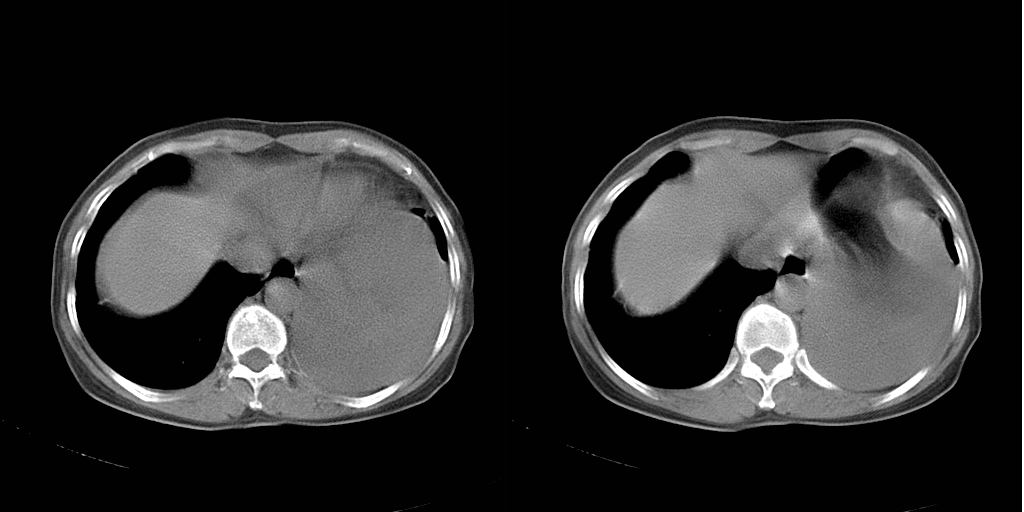

以下是引用dyqct在2007-1-23 15:01:00的发言:[br]左肺下叶实变、略萎陷,近肺门下部密度不均。上腔静脉后及隆突前见肿大淋巴结。余未见异常。[br]考虑:1、左肺下叶中心型肺癌伴肺不张、纵隔淋巴结转移;[br] 2、建议增强扫描并做任意平面重建确定肿块范围及支气管受累情况。

以下是引用同在2007-1-23 19:59:00的发言:[br]左肺下叶中央型肺癌伴肺不张及纵隔淋巴结转移.